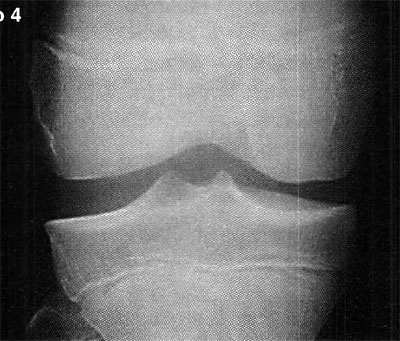

En cuanto a la localización de la lesión, 1 (2,4%) paciente presentó una localización anterior, 12 (29,3%) anterolateral, 23 (56,1%) posteromedial y 5 (12,2%) central. No se pudo explicar claramente esta distribución. (fotos 1 y 2) En cuanto a los casos presentados, los estudios radiográficos pusieron en evidencia la lesión en solo 36,6% de los pacientes, en 26 (63,4%) las radiografías fueron negativas (GI) mientras que de los casos positivos, 6 (14,6%) presentaron una lesión GIl, 6 (14,6 %) presentaron una lesión GIl y 3 pacientes (7,3%) una lesión G IV. (fotos 3 y 4)

Foto 3: RX Lesión G III

Foto 4: Lesión G IV Visualizada en T.A.C.